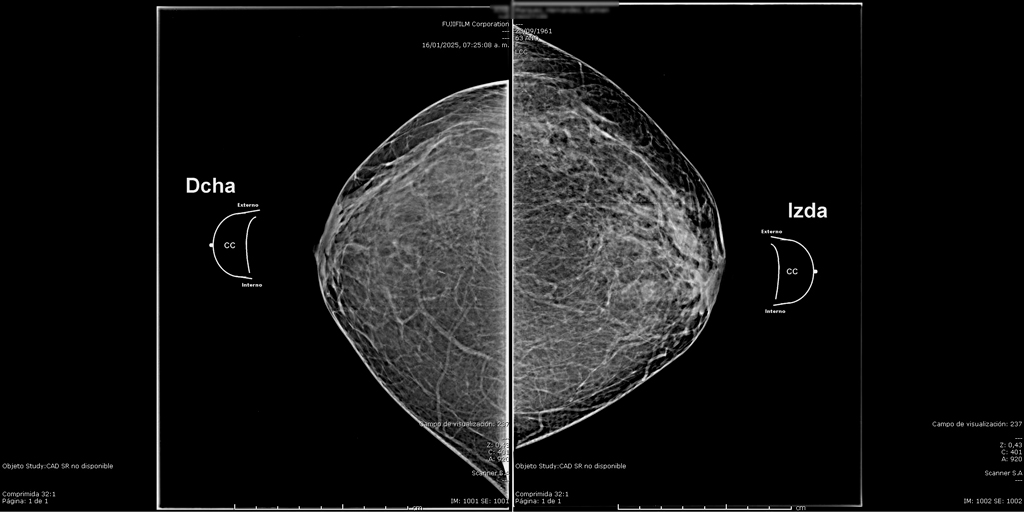

La mamografía es un estudio de diagnóstico por imagen que utiliza bajas dosis de rayos X para obtener imágenes detalladas del tejido mamario. Es una herramienta fundamental para la detección temprana del cáncer de mama y otras patologías mamarias, incluso antes de que sean evidentes al tacto o generen síntomas. Su uso regular en controles preventivos permite salvar vidas al facilitar diagnósticos oportunos y tratamientos más efectivos.

En SCANNER S.A, nuestros equipos digitalizados permiten detectar cambios mínimos en el tejido mamario con alta claridad, permitiendo asi tener un diagnostico preciso y entregar unos resultados reales a nuestros pacientes.